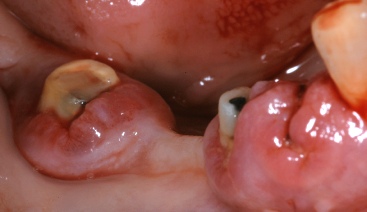

ΧΕΙΡΟΥΡΓΙΚΗ ΕΠΙΜΗΚΥΝΣΗ ΜΥΛΗΣ ΔΟΝΤΙΩΝ ΠΡΙΝ ΤΗΝ ΠΡΟΣΘΕΤΙΚΗ ΑΠΟΚΑΤΑΣΤΑΣΗ

ΠΡΙΝ